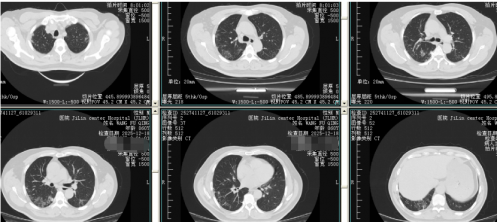

转归:患者一般状态明显好转,咳嗽及咳痰明显减轻,一般活动无受限,外周血氧饱和度在97%以上。12月18日复查肺ct:较12月10日有所吸收,双上肺微小结节基本吸收。予以出院。

12月18日复查肺ct:较12月10日有所吸收,双上肺微小结节基本吸收。